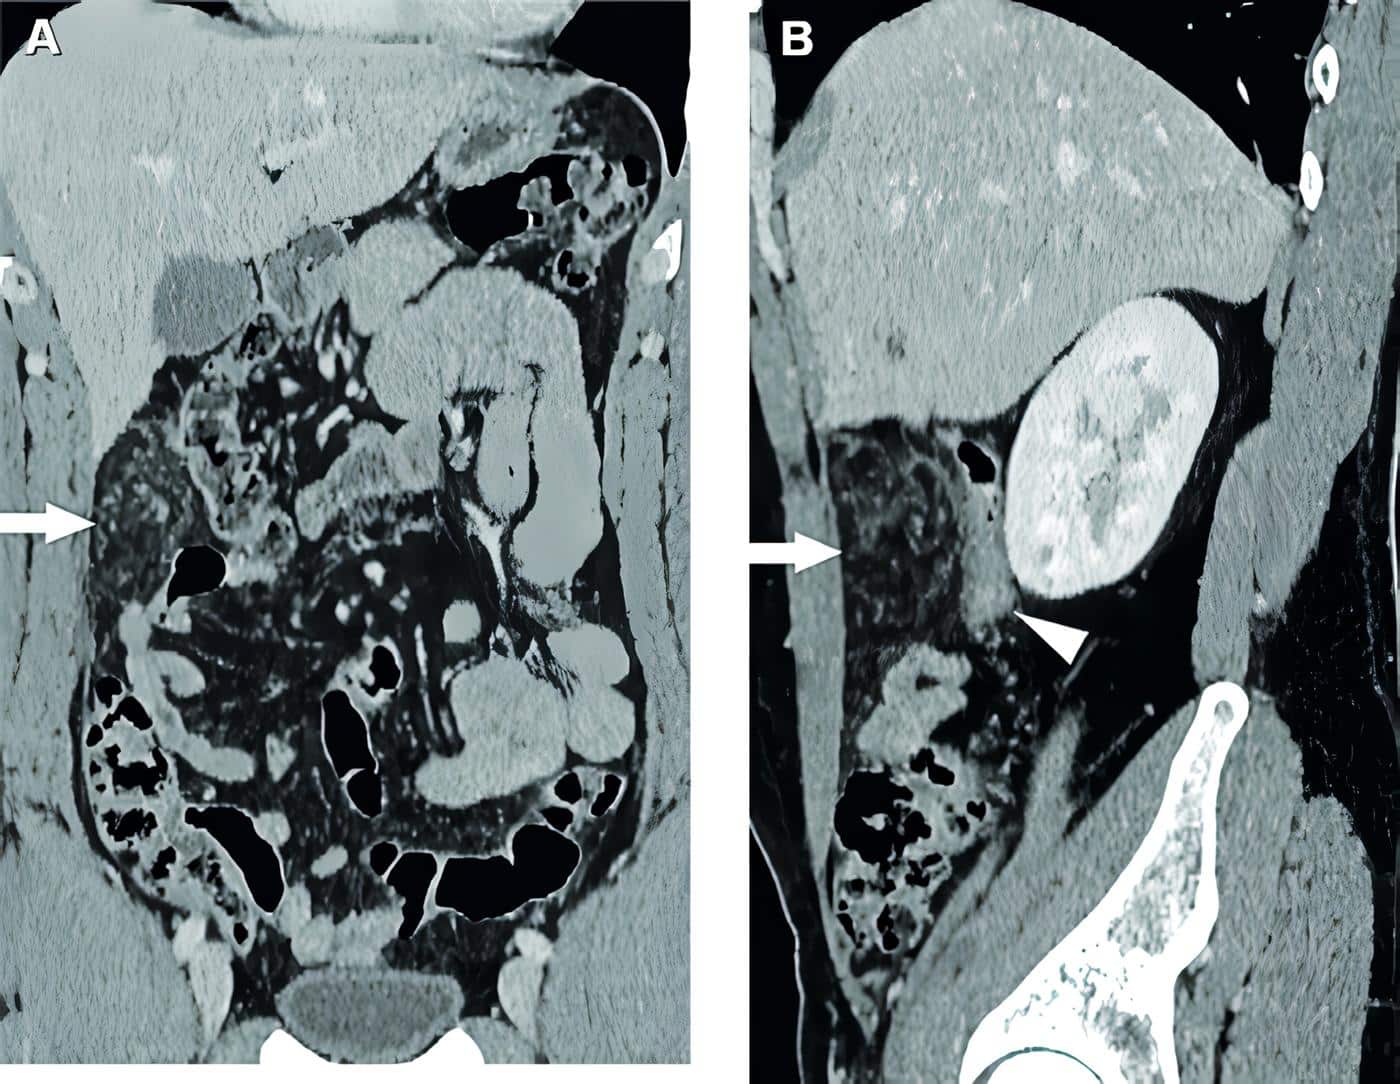

Ante la persistencia del dolor se decidió complementar los estudios con tomografía computarizada de abdomen con y sin contraste intravenoso (figuras 1 y 2) donde se aprecia infarto del omento, para lo que se inicia tratamiento médico conservador.

Figura 1. Tomografía de abdomen con contraste en fase venosa, corte axial, donde se observa a nivel de flanco derecho una alteración en la densidad del epiplón mayor, bien delimitada por un halo hiperdenso (flecha). Contacta hacia atrás con el colon ascendente, el cual presenta paredes discretamente engrosadas, de aspecto inflamatorio, desproporcionadamente menor a la alteración del epiplón (punta de flecha). Fuente: fotografías tomadas por los autores.

Figura 2. Rreconstrucción en plano coronal (A) y plano sagital (B). Alteración bien circunscripta en el epiplón mayor a nivel de flanco derecho (flechas), que determina ligero efecto de masa sobre el colon ascendente (punta de flecha). Fuente: fotografías tomadas por los autores.ABA